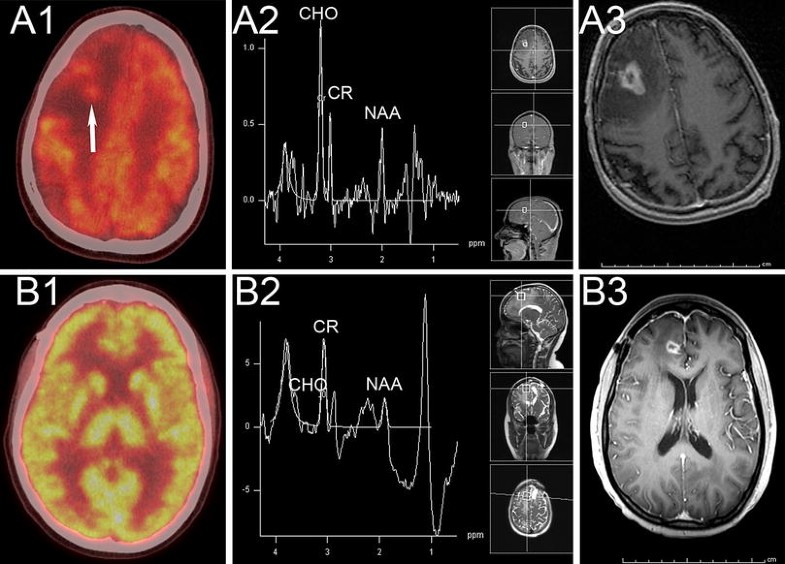

From www.ejradiology.com

Morphological and functional MRI, MRS, perfusion and diffusion changes Radiosurgery Brain Lesions (a) srs alone for 5 to 15 lesions and. Find out whether you might be a good candidate for this alternative to. Stereotactic radiosurgery is a very precise form of therapeutic radiation that can be used to treat abnormalities in the brain and spine, including cancer, epilepsy, trigeminal neuralgia and. Stereotactic radiosurgery should be considered as a valid adjunctive therapy. Radiosurgery Brain Lesions.